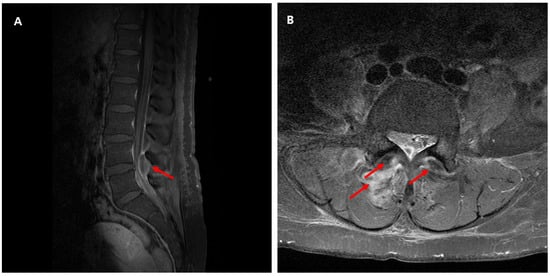

| 3 | F/53 | Lumbar spine disc herniation | Right lower back pain with radiating pain in the right thigh Fever | No | L4-5 | None | None | No | Yes (HD 2) | Ceftriaxone (11 days) → levofloxacin (76 days) | Survived | No | This case |